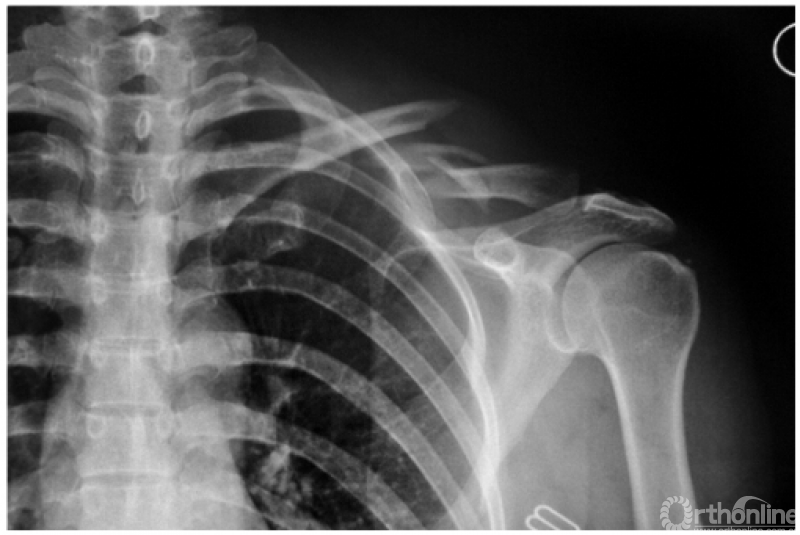

1. 锁骨中段骨折

本例骨折近端因受胸锁乳突肌的牵拉而向后上方翘起,远折端由于喙锁韧带正常而稳定(图1)。